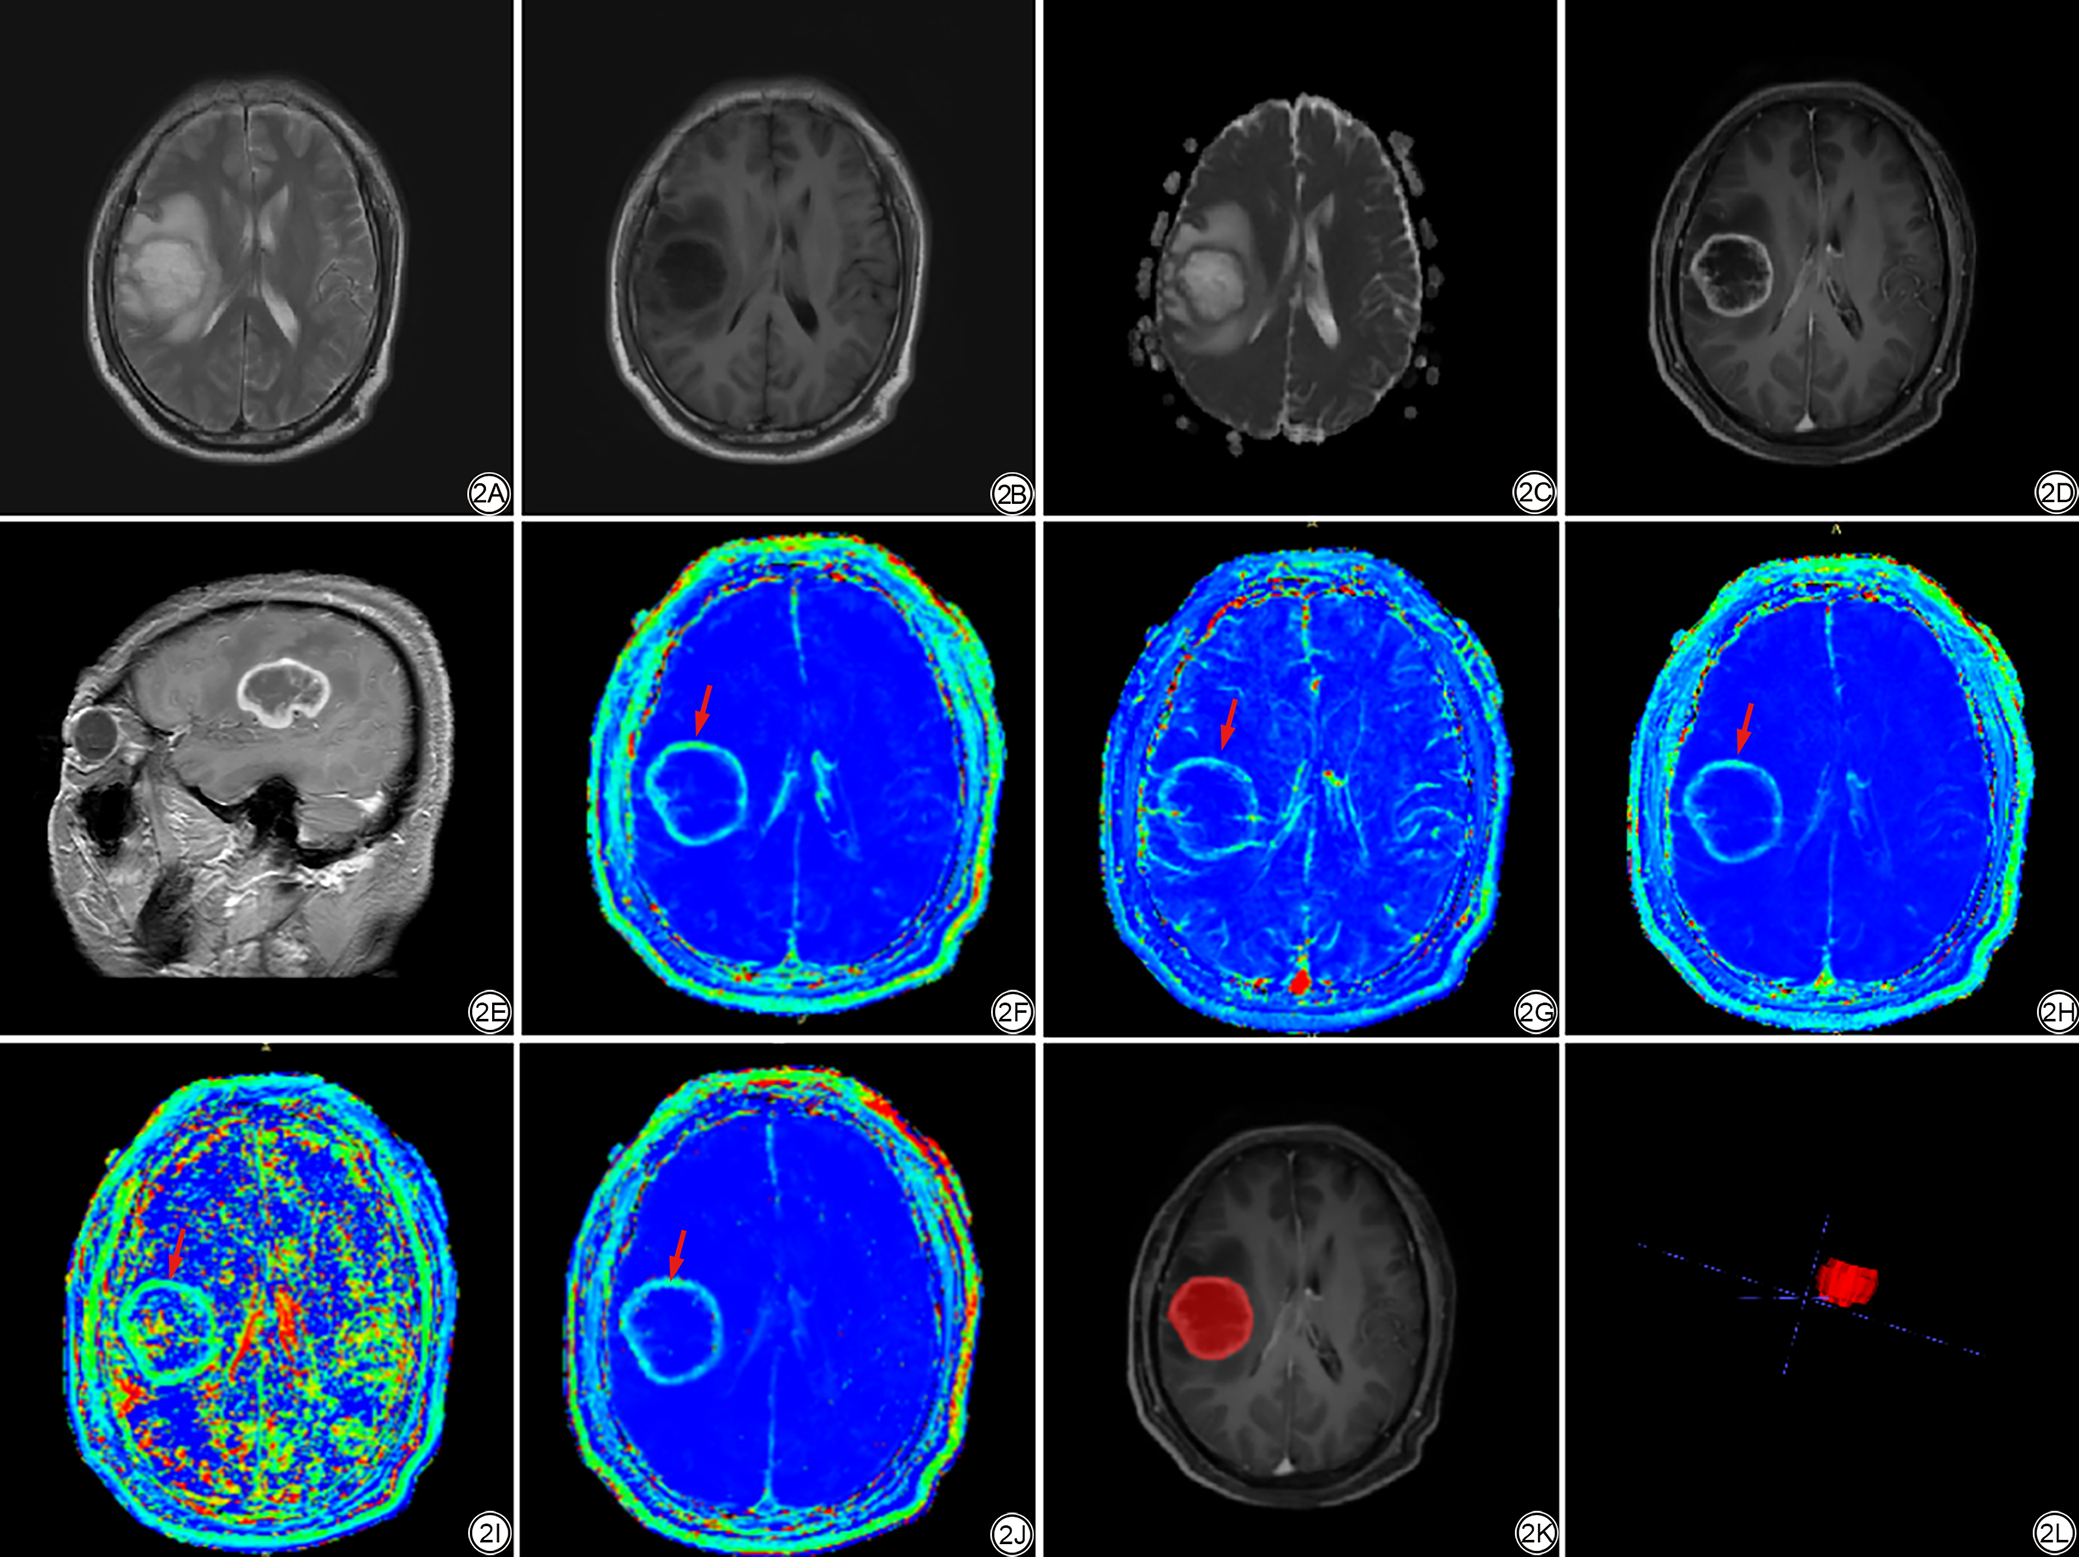

配准完成后,采用ITK-SNAP软件进行感兴趣区(region of interest, ROI)的勾画(图2)。首先由2名分别具有3年(住院医师)、10年(副主任医师)神经放射学经验的放射科医师,在不知晓病理结果的情况下,独立地对所有病例进行ROI勾画。勾画方法为在CE-T1WI图像上沿肿瘤边缘逐层进行全瘤勾画,勾画过程中需仔细去除邻近的大血管、强化的脑膜。另外,高级别胶质瘤部分组织可能存在不明显强化区,此时则参考T2WI进行判断。然后对两位医师的勾画结果进行标注者间一致性分析。使用组内相关系数(intra-class correlation coefficient, ICC)进行量化评估,以确保勾画结果的可重复性和客观性。ICC≥0.75认为一致性较好,若ICC结果具有较好的一致性,则采用具有10年神经放射学经验医师勾画的ROI进行后续分析。

图2  男,47岁,病理证实为高级别胶质瘤。2A:T2WI图像,显示病灶呈高信号,伴明显瘤周水肿;2B:T1WI图像,病灶呈低信号,边界尚清;2C:表观扩散系数(ADC)图;2D:T1WI增强扫描,病灶呈环形强化;2E:T1WI增强扫描(矢状位),清晰显示病灶环形强化的立体形态;2F~2J:动态对比增强(DCE)各参数(Ktrans、Vp、AUC、Kep、Ve)伪彩图,暖色(红、橙、黄等)代表参数值高,冷色(青、蓝等)代表参数值低,肿瘤实性区毛细血管通透性高、肿瘤血管密集呈偏暖色(红箭),内部坏死区毛细血管通透性低、肿瘤血管稀疏呈冷色;2K:肿瘤感兴趣区(ROI)勾画示意图;2L:ROI的三维空间定位图。

Fig. 2  A 47-year-old male patient with pathologically confirmed high-grade glioma. 2A: T2-weighted imaging (T2WI), showing the lesion with high signal intensity and obvious peritumoral edema; 2B: T1-weighted imaging (T1WI), showing the lesion with low signal intensity and relatively clear boundary; 2C: Apparent diffusion coefficient (ADC) map; 2D: Contrast-enhanced T1WI, showing the lesion with ring enhancement; 2E: Sagittal contrast-enhanced T1WI, clearly showing the three-dimensional morphology of the lesion's ring enhancement; 2F to 2J: Dynamic contrast-enhanced (DCE) parametric maps (Ktrans, Vp, AUC, Kep, Ve) in pseudo-color, where warm colors (red, orange, yellow, etc.) represent high parameter values and cool colors (cyan, blue, etc.) represent low parameter values. The solid tumor region exhibits high capillary permeability and dense tumor vasculature, appearing as warm colors (red arrow), while the internal necrotic area shows low capillary permeability and sparse tumor vasculature, appearing as cool colors; 2K: Schematic diagram of tumor region of interest (ROI) delineation; 2L: Three-dimensional spatial localization map of the ROI.